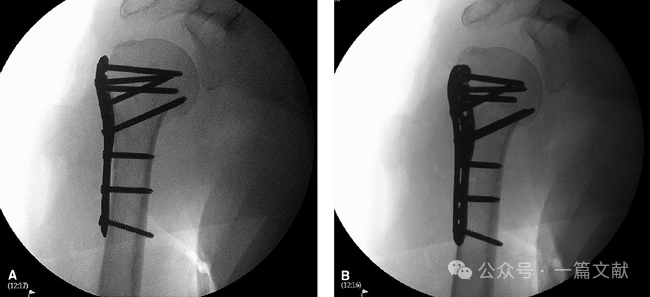

5.3 螺钉穿出是与内固定手术(ORIF)相关的严重并发症,因此需要在多个视图中检查螺钉的长度。固定完成后,应在不同旋转角度下透视影像。可将肱骨从最大外旋至最大内旋角度,分别拍摄以观察之。重点观察螺钉尖端与关节边缘的距离变化:

当螺钉尖端距离关节边缘最近时,应确保此距离>2-3毫米。 如果任何一张透视影像中显现螺钉穿出,则意味着已穿透关节,因为肱骨头是凸面的。 如下图:从肱骨外旋位到内旋位分别拍摄。